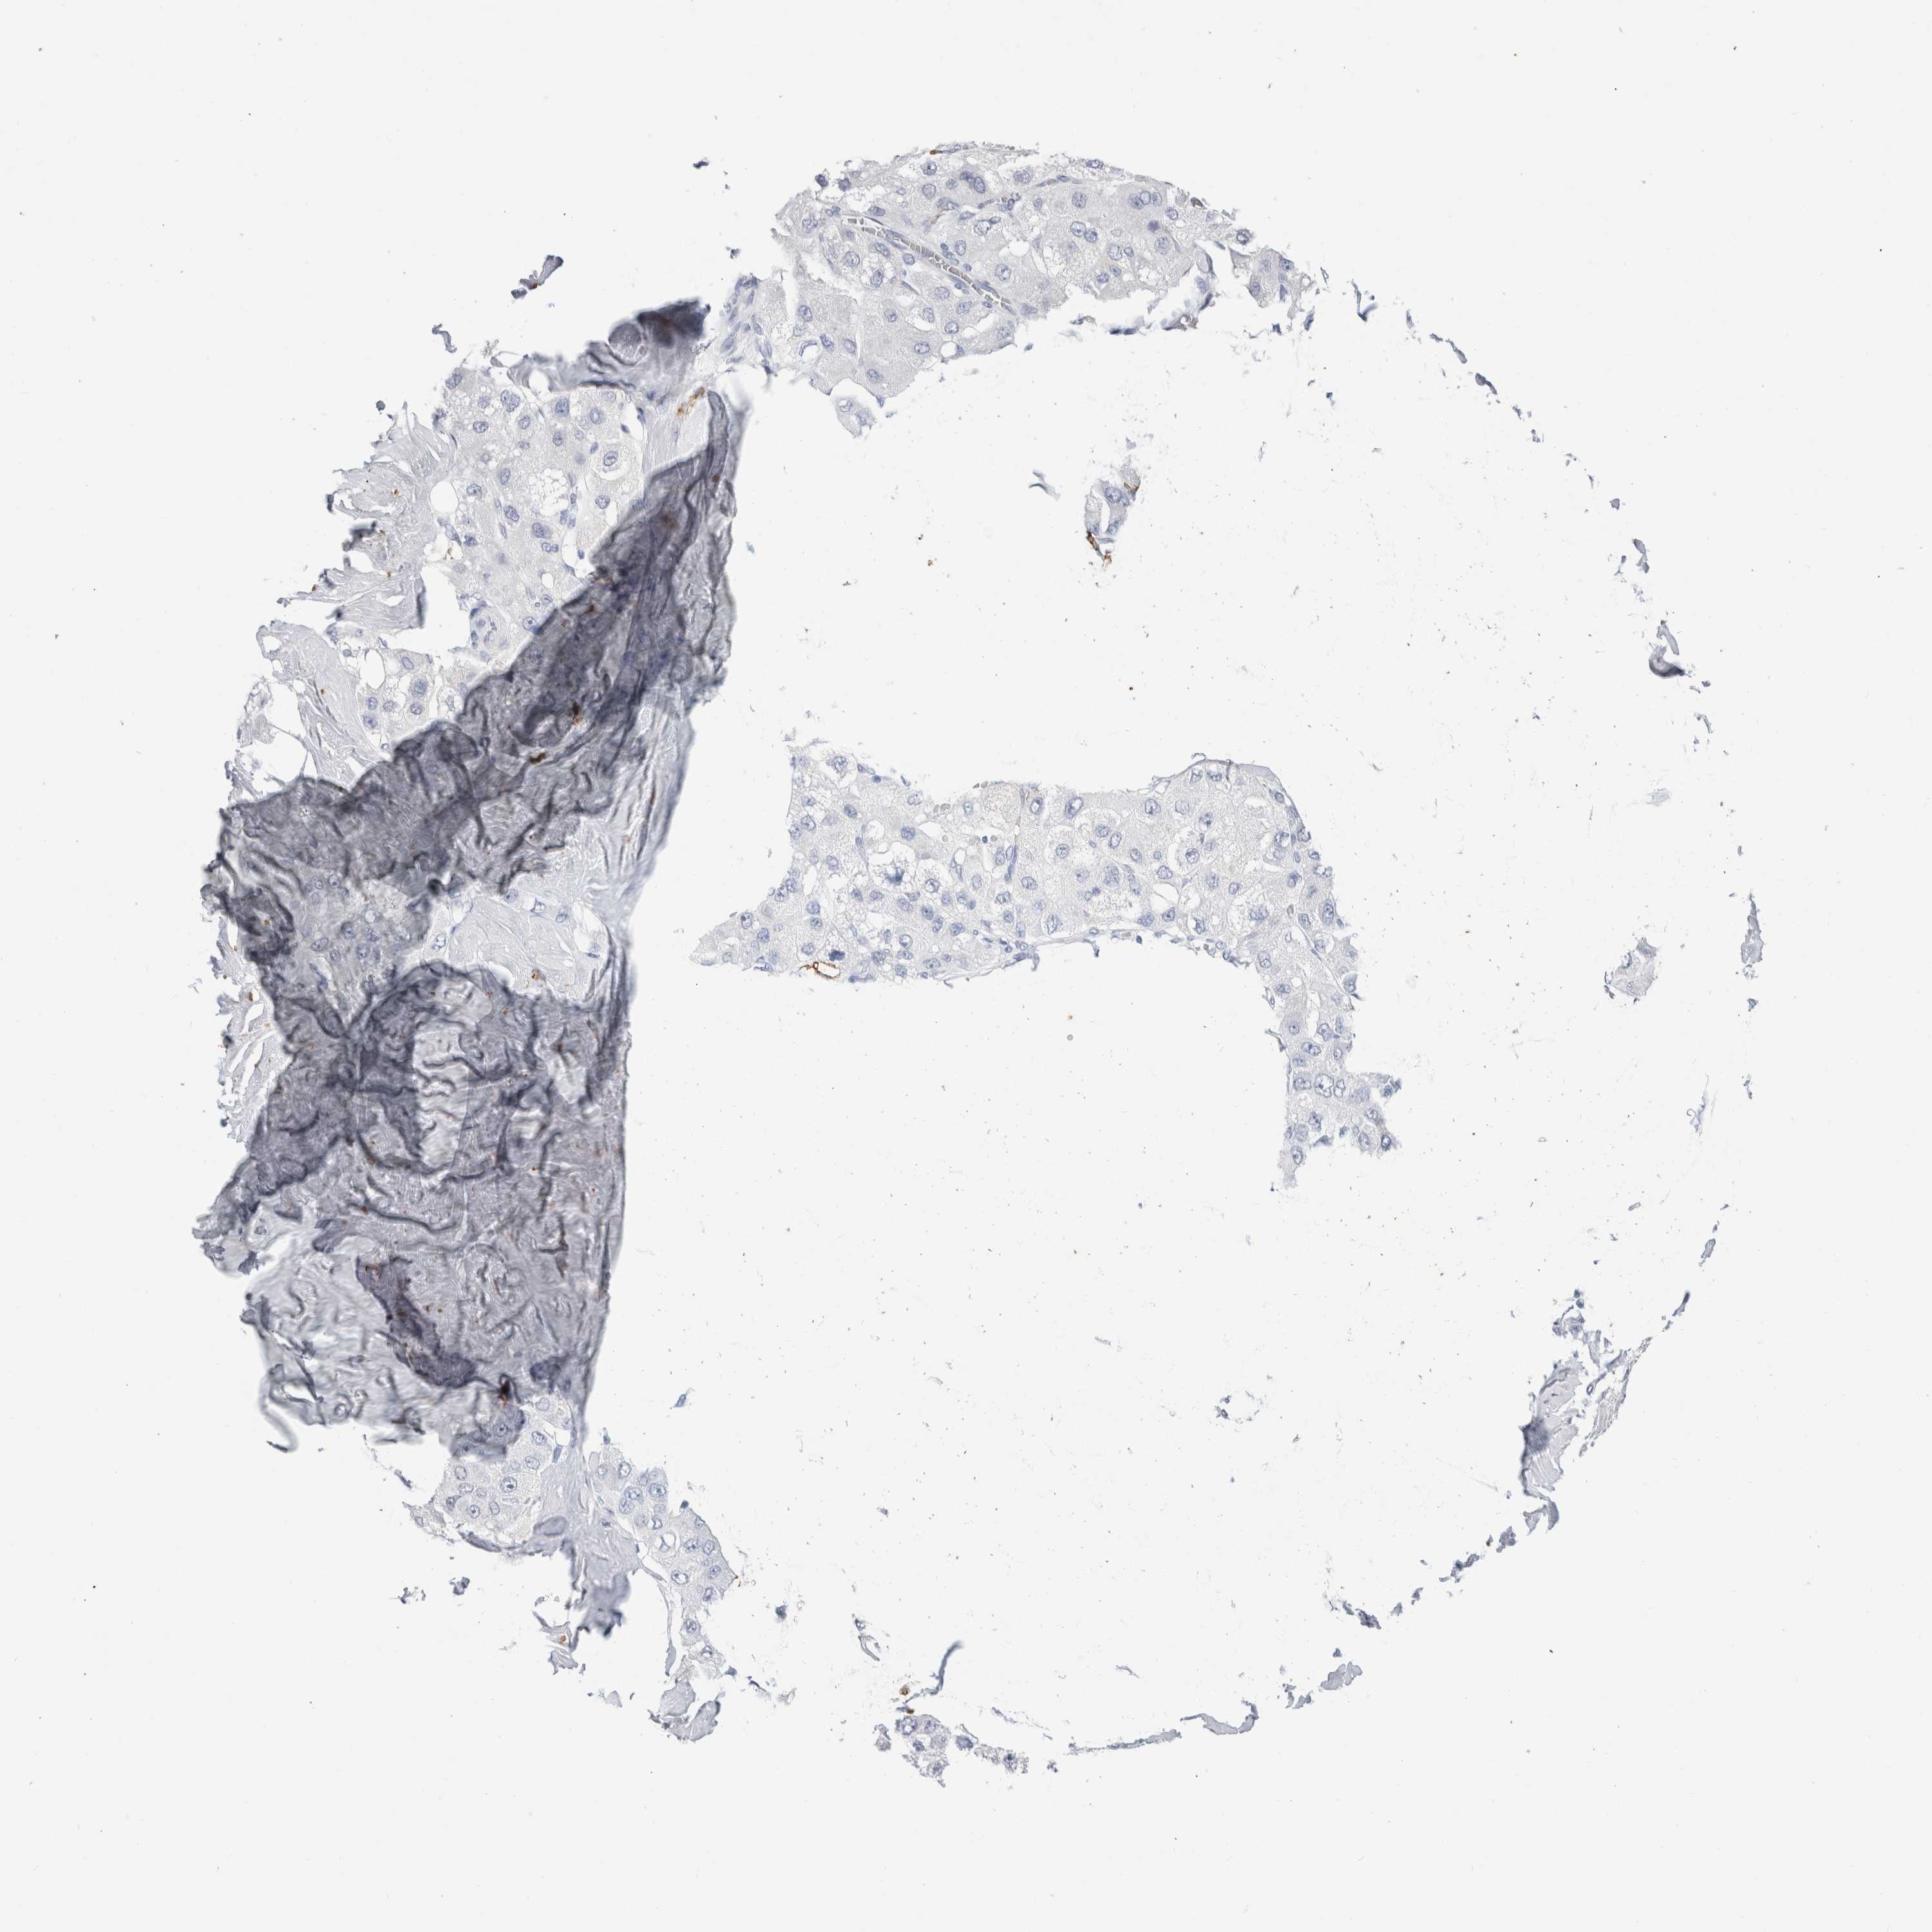

LIVER CANCER - Protein expressioni

A mouse-over function shows sample information and annotation data. Click on an image to view it in a full screen mode. Samples can be filtered based on level of antibody staining by selecting one or several of the following categories: high, medium, low and not detected. The assay and annotation is described here.

Note that samples used for immunohistochemistry by the Human Protein Atlas do not correspond to samples in the TCGA dataset.

Antibody stainingi

Antibody staining in the annotated cell types in the current human tissue is reported as not detected, low, medium, or high, based on conventional immunohistochemistry profiling in selected tissues. This score is based on the combination of the staining intensity and fraction of stained cells.

Each image is clickable and will lead to virtual microscopy that enables deeper exploration of all samples and also displays staining intensity scores, fraction scores and subcellular localization as well as patient and tissue information for each sample.

Antibody HPA022132

Antibody HPA052381

Antibody CAB002493

Antibody CAB025255

Cholangiocarcinoma

Carcinoma, Hepatocellular, NOS